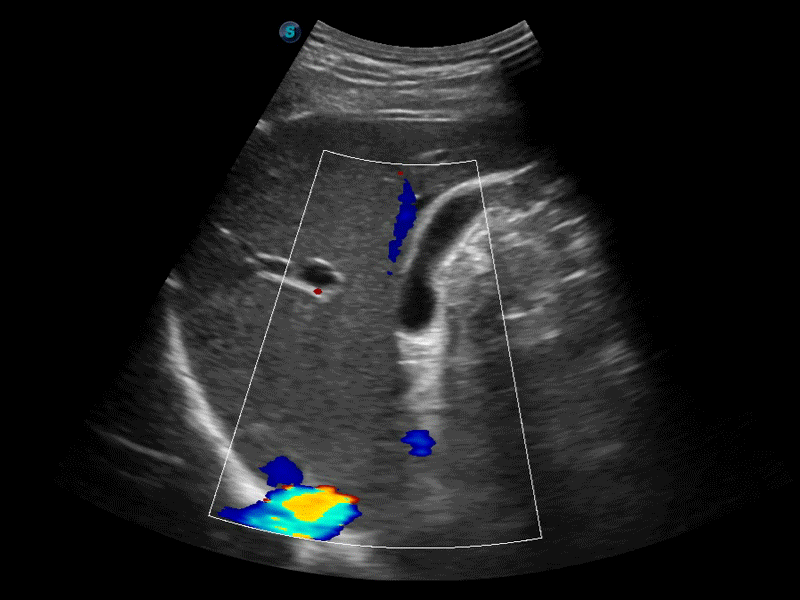

新一代微米成像技术大大提高了器官和病变的可见性。高清对比度分辨率将抑制斑点噪声,同时保持真实的组织结构。

高分辨率血流成像技术提高了对低速血流信号的检测能力。在提高空间分辨率的同时,也克服了血流外溢现象,为用户提供更加真实的血流动力学信息。